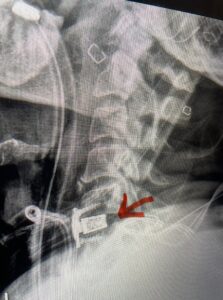

This 61-year-old female with a history of severe osteoporosis and a prior history of a laminectomy from l2-S1 with an L5-S1 instrumented fusion, presents with progressive low back pain and right lower extremity radiculopathy. MRI revealed a grade 1 L2-3 spondylolisthesis with severe stenosis mainly from severe right L2-3 facet joint hypertrophy which was compressing the right L3 descending nerve root. (Fig. 1). She had failed conservative management consisting of physical therapy and pain management with epidurals. She underwent an L1-3 revision laminectomy where we had to dissect a plane underneath the inferior aspect of the L2 lamina. We performed an instrumented fusion at L2-3 with special hydroxyapatite-coated screws to improve fixation to surrounding bone given here severe osteoporosis (Fig. 2) This worked out well and the patient had an uneventful recovery with relief of her leg pain.

Figures 1a: Sagittal and axial T2-weighted lumbar MRIs demonstrating a grade 1 L2-3 spondylolisthesis (red arrow) with severe stenosis secondary to right L2-3 facet hypertrophy (red arrow).

Fig 1b: Note the left L2-3 facet joint (blue arrow) is normal in size compared to the right (red arrow)